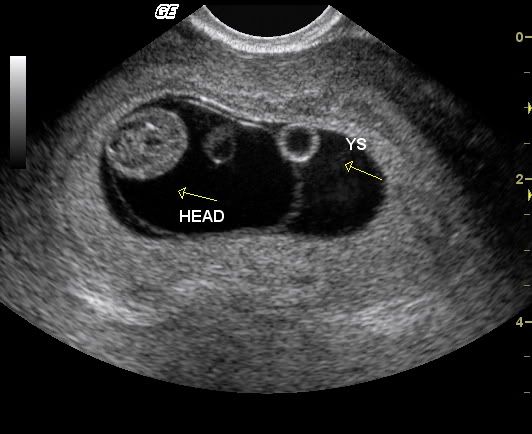

Here are a couple of pics of my grandson. I don't get to hold him until July, but this early peek is nice!

This one is Mommy on the left and Grampa on the right.